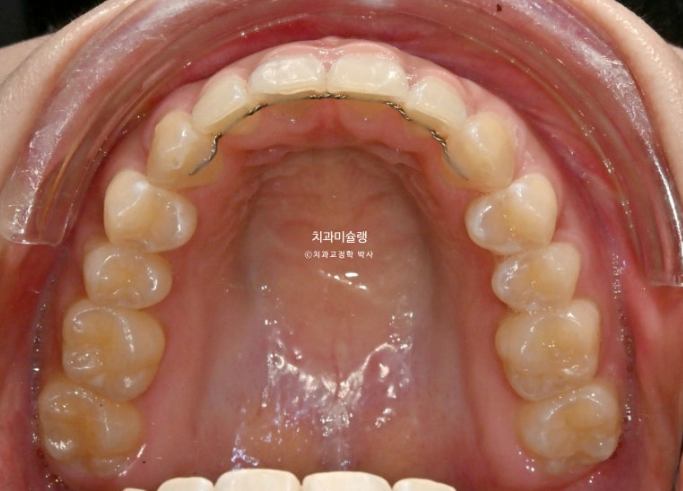

25년 6월 14개 장치를 모두 낀 후 모습입니다.

25.06

어금니 교합을 안정시키기 위한 고무줄 거는 고리가 여럿 붙어있습니다

수술 직후 변색이 되었던 아래 앞니는 신경이 돌아오며 정상 색깔을 회복중입니다.

교합은 좋은편이며

배열도 거의 완성이 되었습니다.